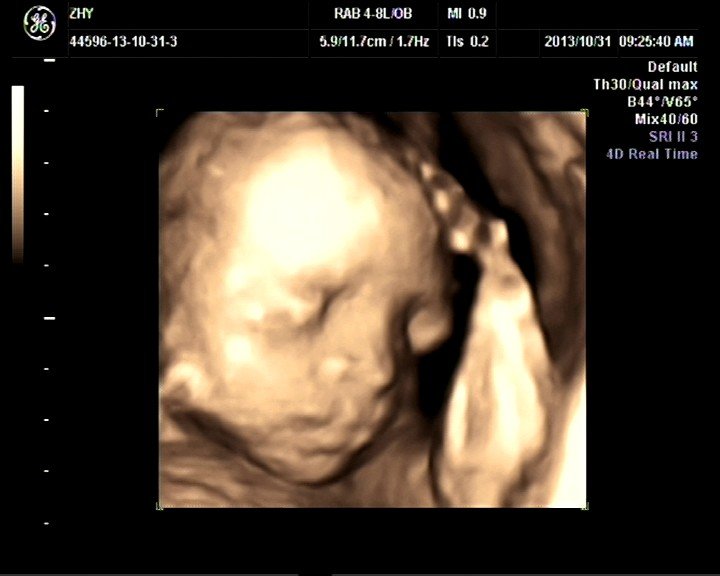

求教!四维彩超数据怎么看胎儿性别?

双顶径:6.7cm   头围24.5cm   侧脑室宽:0.5cm  小脑横径:2.8cm  后颅窝池:0.6cm  腹围:22.1cm  肱骨长径:4.2cm   股骨长径:4.6cm  最大羊水深度:7.5cm   胎动:157/分脐动脉S/D:2.525w..  胎儿实际大小26周,,, 偏大一周。。有高手可以看出宝宝性别吗????好奇死了啊。。。

四维彩超数据和性别没有关系,要看胎儿的生殖器。

你提供的数据表明胎儿发育正常的,但是彩超判断性别是通过直接观察外生殖器外形来看的,你这个只照了脸部当然看不出来了